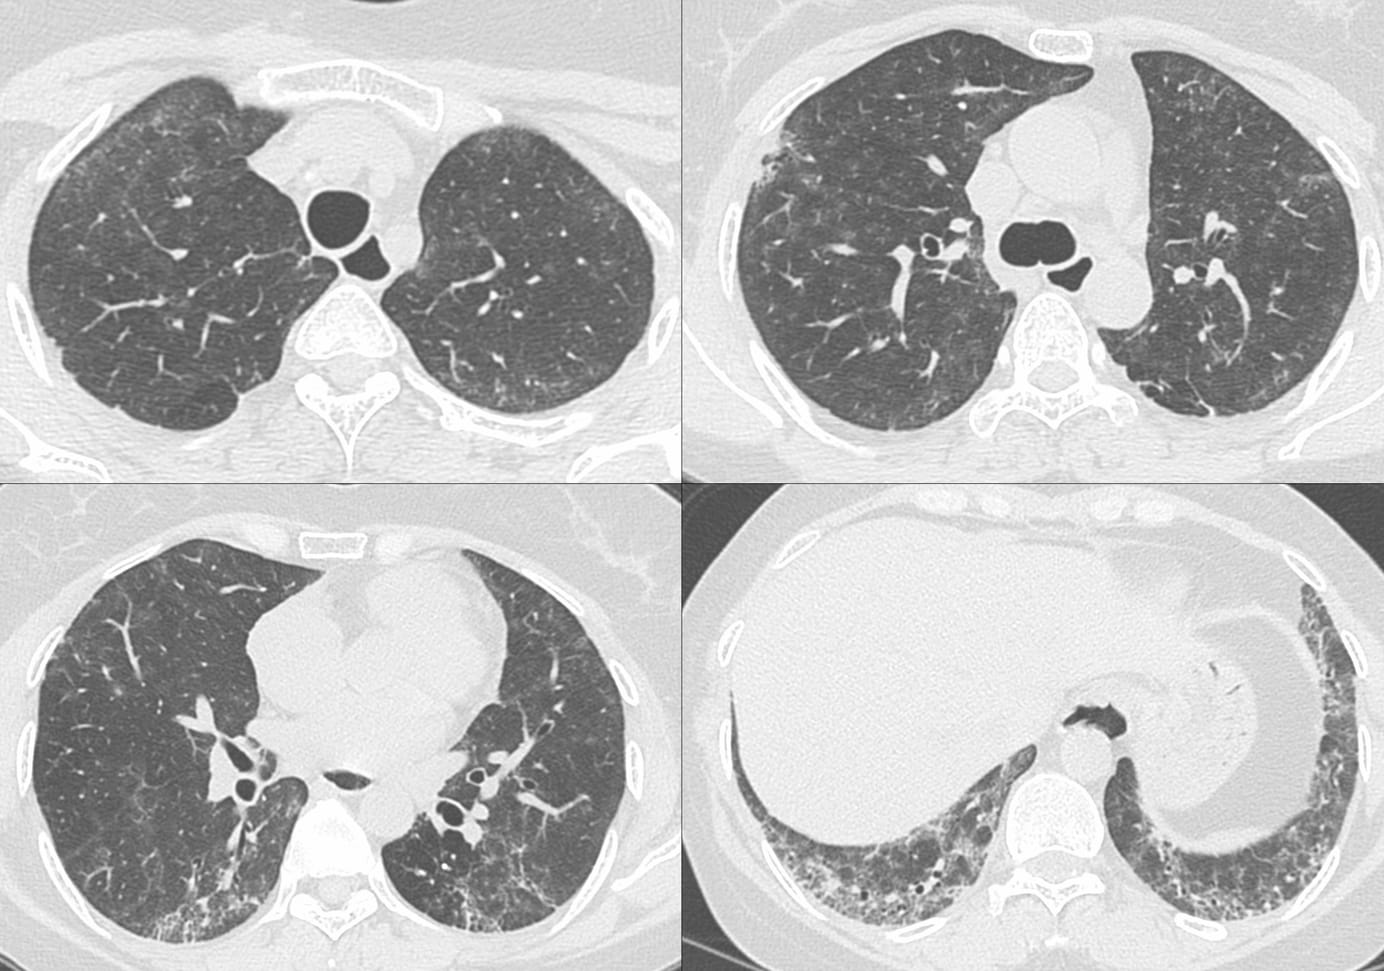

Snippet 06: Six Fibrosing ILD Questions

Six questions that help us understand ILDs

ILD Patterns - The UIP Pattern Paid Members Public

The UIP pattern, characterized by reticular opacities, subpleural basal predominance and traction bronchiectasis with or without honeycombing is the classic fibrosing ILD pattern. Primary UIP implies IPF, while secondary UIP implies other etiologies

COD 131 - The Alveolar Filling Pattern Paid Members Public

The diffuse crazy-paving pattern is quite distinctive in its classic, typical form.